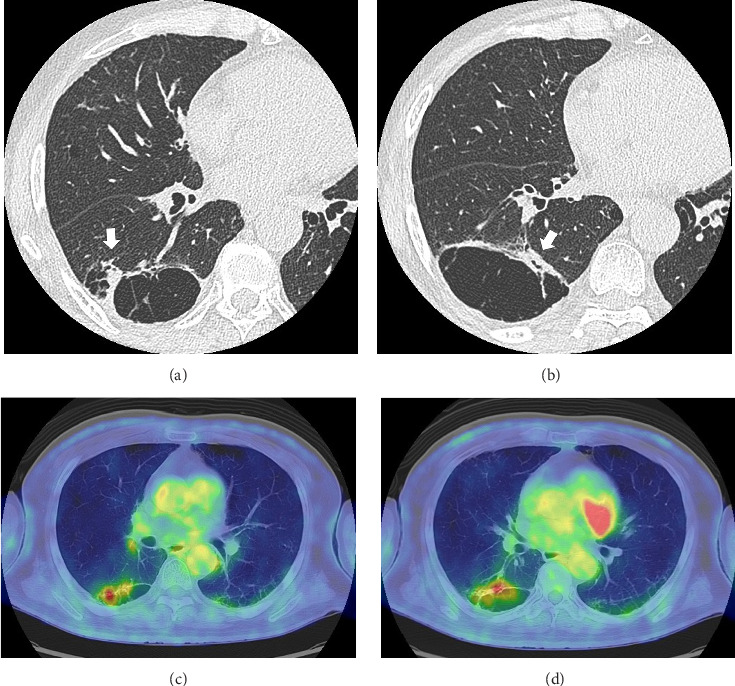

小细胞肺癌(SCLC)合并囊性气隙是罕见的。我们描述的情况下,68岁的男子谁被转介到我们医院,因为在胸部x线检查发现囊性病变。最初的计算机断层扫描显示右下叶膈旁肺气肿引起的小结节邻近囊性空域。组织病理学检查淋巴结病变提示SCLC。化疗后,复发表现为厚壁囊性空腔,囊肿壁有外生结节,类似肺炎。额外的化疗,而不是抗生素治疗,导致壁厚和结节的减少。该病例强调了对抗生素治疗的无反应性,特别是在具有危险因素的患者中,突出了可能延迟及时癌症治疗的诊断陷阱。

Small-cell lung carcinoma (SCLC) associated with cystic airspaces is rare. We describe the case of a 68-year-old man who was referred to our hospital because of a cystic lesion detected on chest radiography. Initial computed tomography revealed a small nodule abutting the cystic airspace due to paraseptal emphysema in the right lower lobe. Histopathological examination of lymphadenopathy indicated SCLC. Postchemotherapy, recurrence appeared as a thick-walled cystic airspace with an exophytic nodule along the cyst wall, mimicking pneumonia. Additional chemotherapy, but not antibiotic therapy, led to a reduction in the wall thickness and nodules. This case emphasizes unresponsiveness to antibiotic therapy, especially in patients with risk factors, highlighting the diagnostic pitfall that may delay timely cancer treatment.